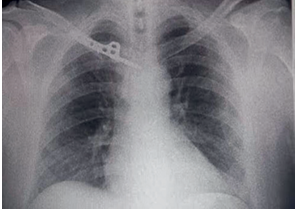

43-year-old male patient, with no significant history, who after a motorcycle traffic accident, presented trauma to the posterior region of the right shoulder, presented pain, increased volume, functional limitation and deformity in the right sternoclavicular region for 4 days. Upon physical examination, there were no signs of vascular injury or respiratory distress, and no nor deformity in the posterior shoulder region with no signs of phlogosis. Imaging studies were evaluated based on anteroposterior chest X-ray, which showed (Figure 1) a fracture in the medial third of the clavicle with a simple displaced articular trace. The Constant score was applied, according to which where pain, current and active mobility and power were evaluated with a result of 24 points (bad).

Figure 1

Figure 1. X-ray showing displaced right medial clavicle joint fracture.